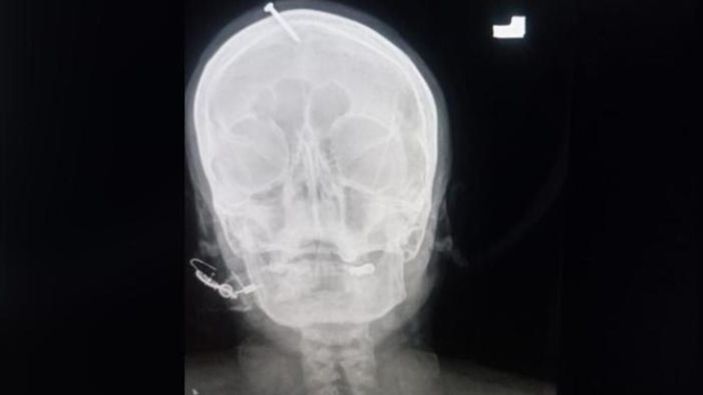

Doktor Haider Khan, hamile kadının çiviyi kafasından pense ile çıkarmaya çalıştığı ancak başaramayınca hastaneye geldiğini açıkladı. Khan, "Buraya geldiğinde bilinci tamamen açıktı ama çok acı çekiyordu. Şifacı karnındaki bebeğin kız olduğu ultrasonla kanıtlanmasına rağmen ona erkek çocuk sahibi olabileceğini söylemiş ve kafasına çivi çakmış. Çekilen röntgen çivinin kadının kafasının üzerine çakıldığı ancak şans eseri beyni ıskaladığını gösterdi." dedi.

RÖNTGEN GÖRÜNTÜLERİ ÇIKTI

Doktorlar, kadının kafasındaki çiviyi yaptıkları ameliyatla çıkardı. Çekilen röntgen görüntüleri ise sosyal medyada hızla yayıldı. Görüntüler sonrası devreye giren polis, her yer de şifacı kadını arıyor.